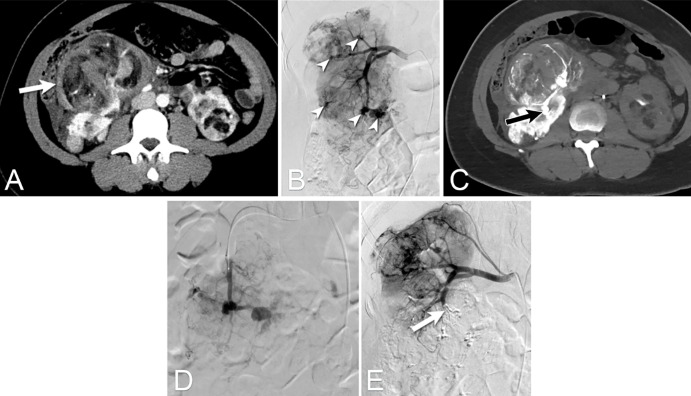

Figure 8:

Images from CT fluoroscopy for embolization followed by ablation and stabilization of lytic bone tumors in a 66-year-old man with thyroid cancer metastatic to the left glenoid bone. (A, B) PET/CT scan shows the metastasis (arrow) resulting in both resting and mechanical pain that severely impaired the quality of life. Given the large size, comparative hypervascularity to surrounding muscle, and location adjacent to the shoulder joint, a comprehensive combination treatment using angio-CT was pursued. (C) Image from fluoroscopically guided embolization performed via left radial artery access shows pre-embolization tumor blush (arrow). (D) Successful embolization of the tumor with minimal residual tumor blush (arrow). After the embolization, the patient was immediately repositioned prone. (E, F) CT scans show the cryoablation of the tumor and the therapeutic ice ball (arrow in E), which was followed by percutaneous injection of polymethyl methacrylate for stabilization, and demonstrate cementoplasty results filling tumor void in the glenoid bone (arrow in F). The patient regained range of motion in the shoulder, with ability to hyperextend the arm above the head. (G, H) Follow-up CT scans 18.5 months after the procedure demonstrate stability of the treatment area, without progression of fracture or tumor.

Figure 9:

Images from integrated fluoroscopy and CT for palliative treatment in an 87-year-old woman with cholangiocarcinoma metastatic to the iliac bone. (A, B) Images from contrast-enhanced CT and MRI, respectively, show the metastasis (arrow) resulting in both resting and mechanical pain that severely impaired quality of life. Given the large tumor size and instability from the osseous defect, a comprehensive combination treatment with local-regional control by cryoablation followed by fixation by internal cemented screw procedure was pursued. (C) Image from CT-guided cryoablation performed via a posterior approach shows the cryoprobe placement (arrow). After completion of cryoablation, (D) fixation and injection of polymethyl methacrylate (PMMA) cement was performed under fluoroscopic guidance. Image shows screws and cement needle (arrow). (E, F) Oblique sagittal and axial postprocedure CT images confirm screws and PMMA (arrows).